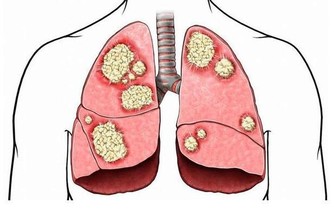

3.氣管炎

秋季氣管炎高發通常是由於上呼吸道感染了病毒所致。秋季天氣複雜多變,如果寶寶體溫變化過快,吸入煙塵、花粉、羊毛等刺激性物質都可能引起寶寶支氣管感染。寶寶患氣管炎主要症狀是大聲哭鬧,有痰鳴音,寶寶煩躁時,咳嗽會加劇,喘鳴音也會變得響亮。